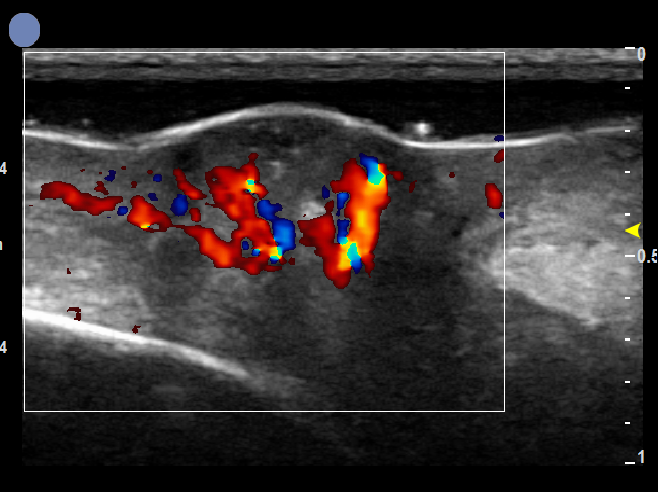

基于全球领先的CMUT半导体超声技术,集成近60项发明专利,珂纳医疗历经数年潜心研制,推出了Paragon XHD便携式彩色多普勒超声系统。该系统显微镜级的成像分辨率,为临床医生观察诊断表皮、真皮、皮下组织及皮肤附件提供了清晰的二维图像。丰富灵敏的彩色多普勒血流成像,满足了对于皮下血流,皮肤肿瘤状态的判定。方便实时的无创操作深受医生和患者青睐,为术前切缘深度测量,术后疗效评估以及医美玻尿酸注射引导等提供了极具价值的诊断信息。